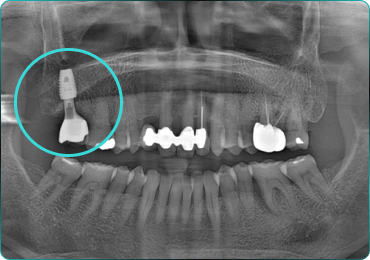

뼈와 임플란트를 한번에!

뼈플란트, 그 결과의 차이를 경험해보세요!

67세 여성

After